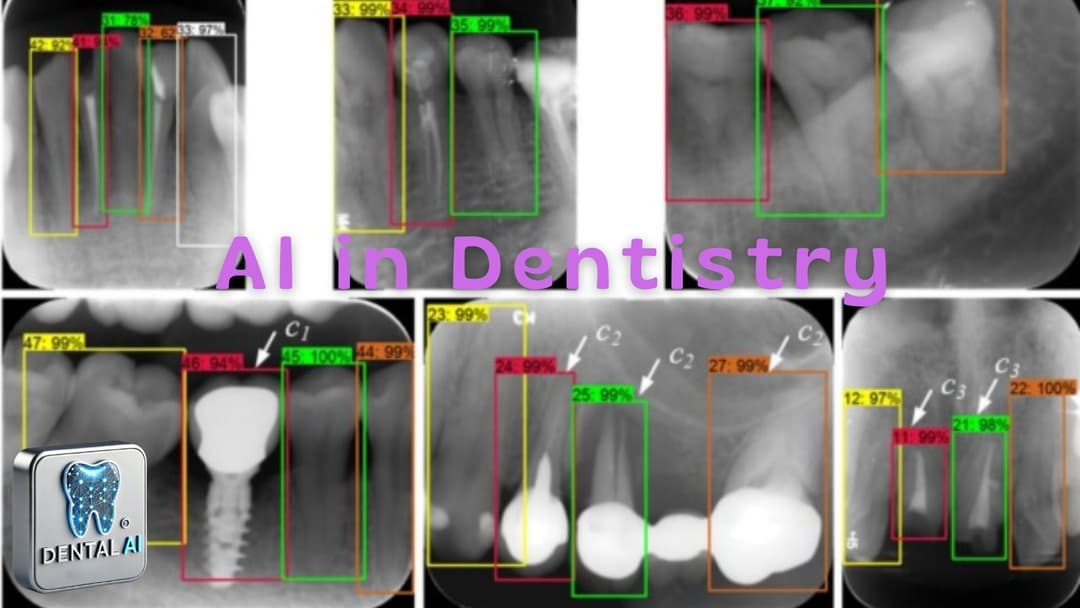

Assessment of YOLOv3 for caries detection in bitewing radiographs based on the ICCMS™ radiographic scoring system Authors: Wannakamon Panyarak, Wattanapong Suttapak, Kittichai Wantanajittikul, Arnon C...

A deep learning approach to automatic teeth detection and numbering based on object detection in dental periapical films Authors: Hu Chen, Kailai Zhang, Peijun Lyu, Hong Li, Ludan Zhang, Ji Wu, ChinHu...

An Enhanced Tooth Segmentation and Numbering According to FDI Notation in Bitewing Radiographs Authors: Buse Yaren Tekin, Caner Ozcan, Adem Pekince, Yasin Yasa Summary This study introduces a deep lea...

A Comprehensive Artificial Intelligence Framework for Dental Diagnosis and Charting Authors: Tanjida Kabir, ChunTeh Lee, Luyao Chen, Xiaoqian Jiang, and Shayan Shams Summary Kabir et al. proposed a co...